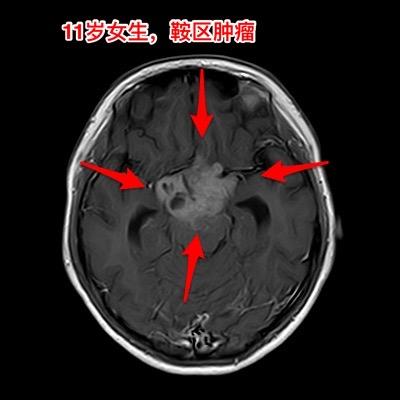

警惕小儿脑肿瘤。小孩子如果长了鞍区肿瘤,一般都会出现症状,一旦有了症状家长及医务人员就要足够重视,才能及时找到病因。 今天介绍的小孩子,肿瘤发现的就晚了。 11岁四川女孩子,因多饮多尿3年半,视力下降9个月,行走不稳、贪睡一个月发现鞍区肿瘤,急忙到北京来就医。 三年前开始出现多饮多尿症状,夜间上厕所好几次,到医院检查没有发现肾脏问题,就没有继续查找原因。 近两年身高增长缓慢,到医院化验显示生长激素缺乏,在当地医院注射生长激素治疗,没有查找生长激素